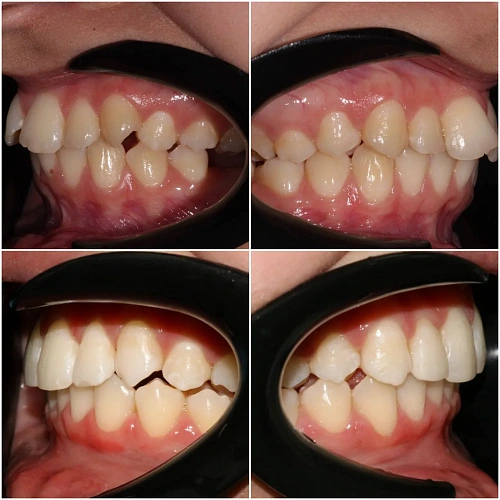

Нарушение соотношения челюстей и неправильное положение зубов — зубные ряды смыкались некорректно, зубы стояли со смещением.

Зубы выровнены, смыкание нормализовано. Установлены несъёмные ретейнеры на обе челюсти, изготовлены ретенционные капы. Пациентка предварительно проконсультирована ортопедом онлайн.

Решение: Поставили элайнеры 3D Smile на обе челюсти. Лечение заняло 4 года и потребовало нескольких последовательных этапов коррекции. Капы менялись каждые 1–2 недели, на контрольных визитах отслеживали прогресс и выдавали новые наборы. Зубы встали в правильное положение, смыкание нормализовалось. Зафиксировали ретейнеры на обе челюсти, изготовили ретенционные капы. Пациентка прошла онлайн-консультацию с ортопедом для оценки дальнейших шагов.